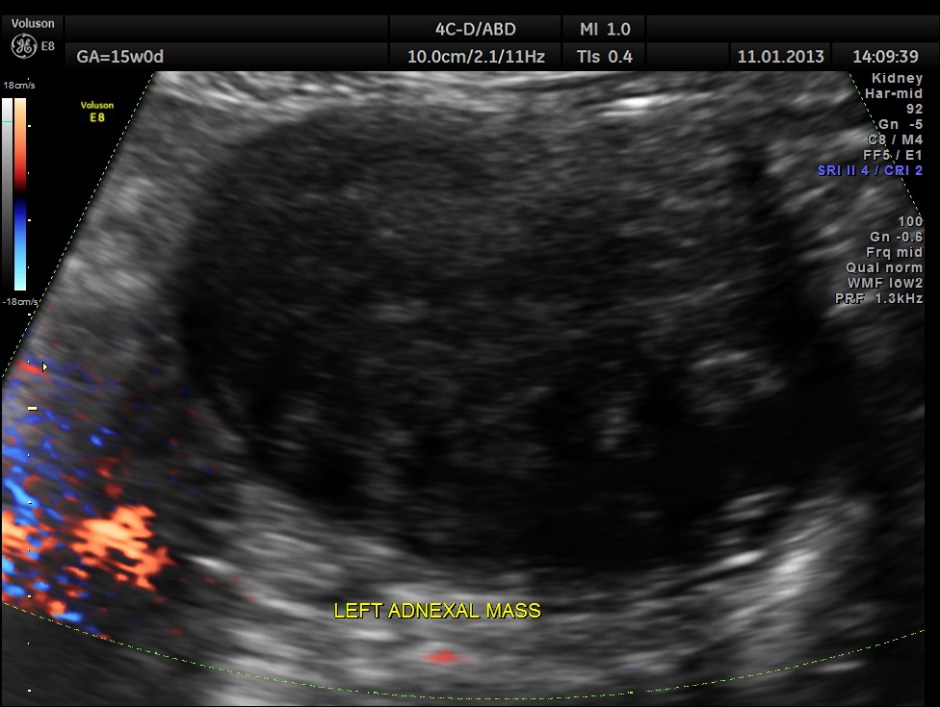

Left adnexal solid mass was seen.

So this patient was taken up for surgery because of the clinical presentation of acute pain , probably torsion. The mass lesion was removed and the pathologist reported it as PARA OVARIAN FIBROMA . The pregnancy was continued normally and was uneventful . The fetus showed mild bilateral pelvi ectasis persistently from 28 weeks onwards till delivery. Scan done 1 month after delivery showed normal kidneys in the child.